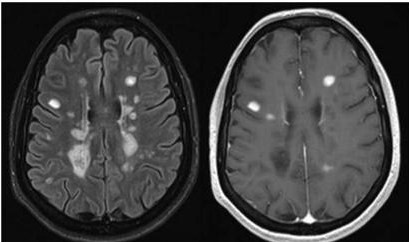

Esclerosis Múltiple: Cuando el paciente es terapeútico

La Esclerosis Múltiple (EM) es una enfermedad crónica del sistema nervioso, caracterizada por la pérdida de la vaina de mielina de las neuronas…